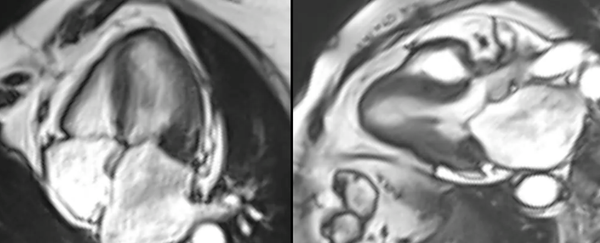

Case 246 - A Mitral Valve Mass

A tumor protocol cardiac MRI often allows a definite diagnosis to be made as in this case.